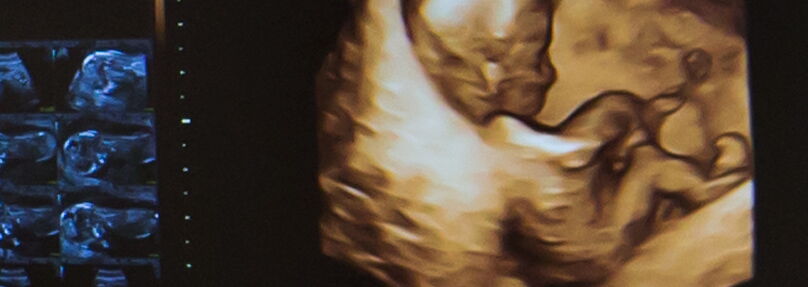

In der Schwangerenbetreuung wird in gleicher Weise neueste Ultraschalltechnik eingesetzt. Etablierte Methoden der Pränataldiagnostik wie zum Beispiel der nichtinvasive Pränataltest (NIPT) oder Farbdoppler gestützte Ultraschalluntersuchungen ermöglichen eine sehr genaue Beurteilung der Gesundheit des Kindes. Unser High-End-Ultraschallgerät ermöglicht faszinierende 3D- bzw. 4D-Bilder/-Filme sowohl in der Frühschwangerschaft als auch im weiteren Schwangerschaftsverlauf.